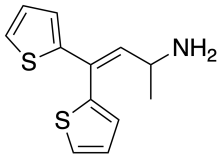

Thiambutenes

Structures